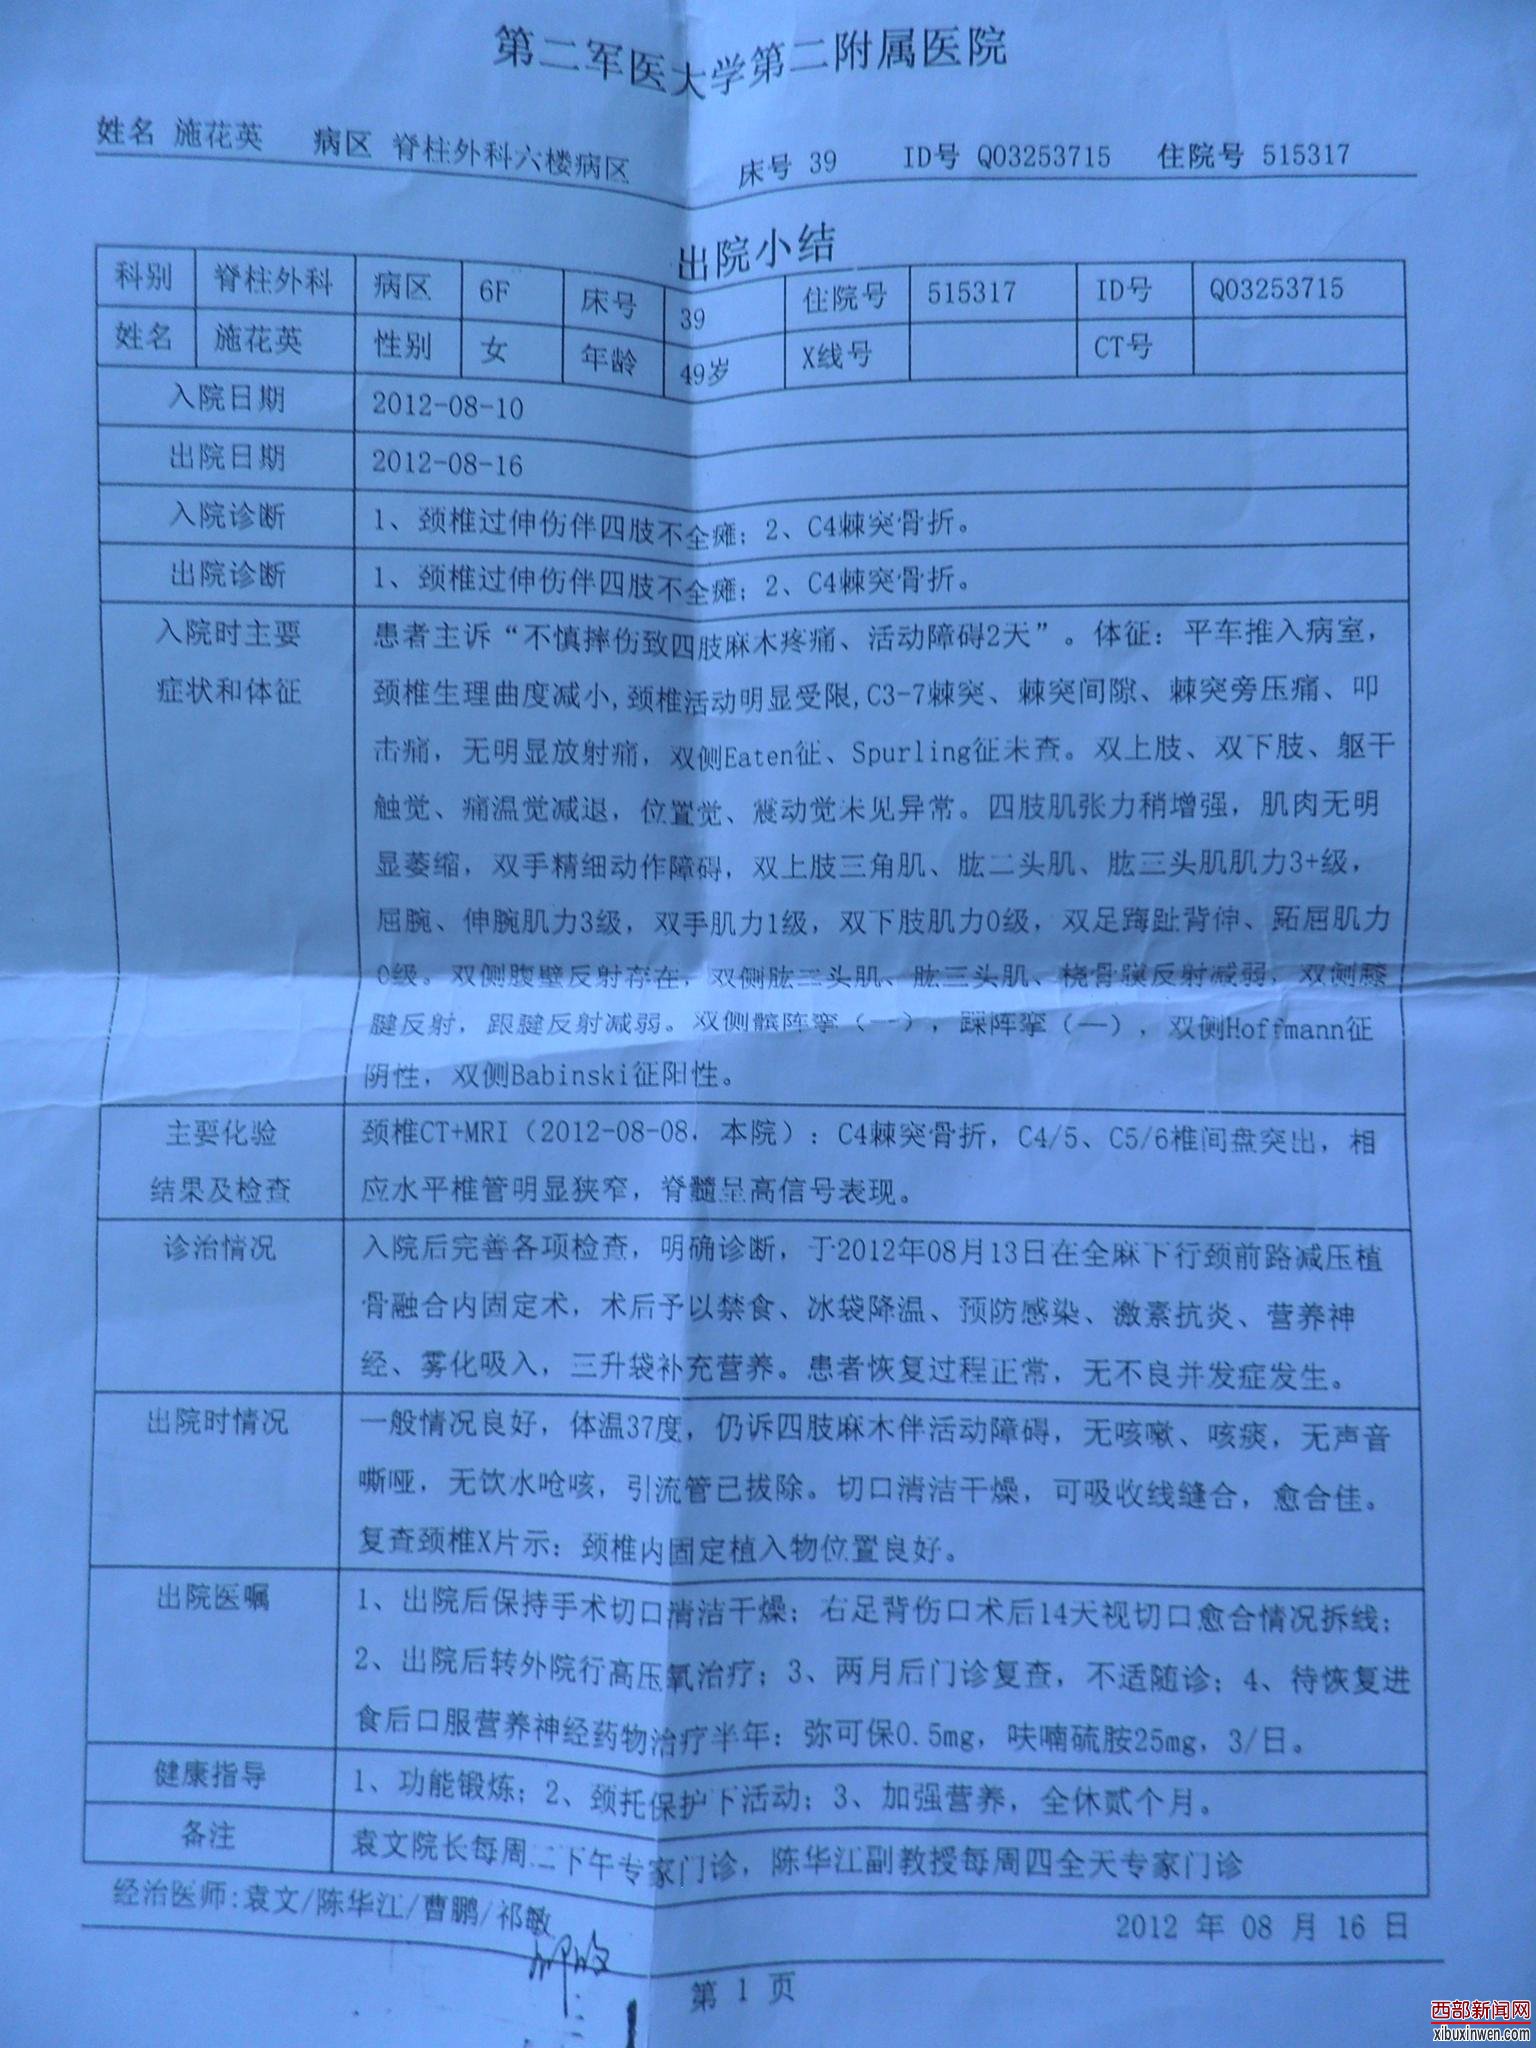

2012年8月8日,我妈摔成高位截瘫,转送多家医院,后送至上海市长征医院,医院的片子出来后,所有的医生都紧张:照片子的情况来看,我妈的第四第五根颈椎粉碎性骨折并把中枢神经给压死了一段。医生说:如果桑兰能站我妈妈就能站,除非有奇迹!我和我爸都崩溃了。还说:我妈的神经已经死了一部分,神经死了是不会恢复的。于8月13日经骨科袁文、陈华江、曹鹏、祁敏等医生做了植骨固定术,当时长征医院的住院号515317。

后8月16日转院至上海复旦大学附属金山医院。于2012年9月18日在中医科杜玉玲、杨奕平、谢珉宁、张磊等医生,康复科黎明、董桂荣、杨颖、杨天麒等医生联合张惠忠先生和他的科研团队,运用维生素C、维生素B6针剂、固齿强骨胶囊等,并在李华等护士们的精心照顾下,采用了最先进的细胞营养疗法,当时金山医院的住院号332551。现在我妈妈四肢能运动能走路了。